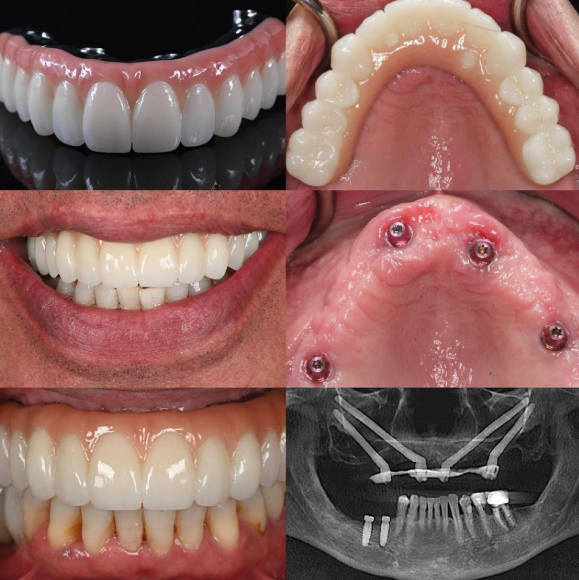

In 2026, zirconia dental implants have emerged as a game-changing all-ceramic option for the maxillary and mandibular anterior zones, where esthetics, soft-tissue harmony, and long-term predictability are paramount. Unlike traditional titanium, zirconia’s tooth-like white color eliminates gray shadowing through thin gingival biotypes, delivering superior pink and white esthetic scores while maintaining high biocompatibility and low bacterial adhesion. Recent long-term data confirm survival rates rivaling titanium in carefully selected cases, with monolithic zirconia restorations simplifying workflows and reducing complications. This evidence-based guide synthesizes 2025–2026 clinical studies to outline breakthroughs, case selection, and protocols for optimal outcomes in the esthetic zone.

Zirconia implants—primarily one-piece or two-piece yttria-stabilized tetragonal zirconia polycrystal (Y-TZP)—offer metal-free solutions that address patient demands for natural-looking restorations. Advances in surface modification (sandblasted and acid-etched ZLA surfaces) and CAD/CAM monolithic designs have narrowed the historical gap in osseointegration and mechanical performance, making them ideal for high-smile-line patients, thin biotypes, and those with metal sensitivities.

Modern zirconia implants feature optimized micro-rough surfaces that promote osseointegration comparable to titanium in short- to medium-term studies. Flexural strength exceeds 900 MPa, while the white hue ensures excellent light transmission and fluorescence matching natural dentin-enamel. Monolithic zirconia crowns or abutments eliminate veneering chipping risks, with high-translucency formulations now rivaling lithium disilicate in anterior esthetics.

Subgroup analysis confirms zirconia excels in anterior esthetics: higher PES scores and zero metal visibility even with minor recession. While some studies note slightly lower overall survival than titanium in high-load scenarios, strict case selection and late placement protocols yield titanium-comparable results in the esthetic zone.

Restoration: Monolithic high-translucency zirconia crowns—screw-retained for retrievability or cement-retained on zirconia/titanium bases. Adhesive protocols (MDP primers) ensure retention. Occlusal adjustment via digital analysis prevents overload.

Zirconia implants in the aesthetic zone represent a 2026 paradigm shift toward fully ceramic, patient-centered implantology. With 10-year survival rates up to 97.7%, stable bone levels, superior esthetics, and high patient satisfaction, they deliver predictable, metal-free solutions where natural harmony matters most. By aligning material properties with case-specific demands—thin biotypes, high smile lines, and esthetic priorities—clinicians achieve outcomes that rival or exceed traditional options while future-proofing practices.